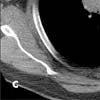

The CT image at the level of the aortic arch confirms the presence of a mass in the anterior mediastinum that displaces the trachea posteriorly (C, arrow). The superior vena cava is not visible; it has probably been compressed or invaded by the large mass. In a second CT image (D), minimally more inferior at the level of the azygous arch, the superior vena cava is again not visible and the azygous vein is densely opacified (arrow).

Figure C

Figure D